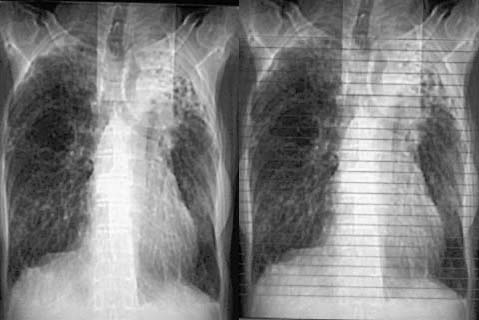

以下是引用zjzjr在2008-5-2 14:39:00的发言:[br]支持双侧继发型肺结核,左侧胸膜肥厚,慢性支气管炎伴间质纤维化.

以下是引用有风的日子在2008-5-2 12:13:00的发言:[br][emb10][br][br]肺ca?有病理支持吗?[br][br]我看更象是肺tb并支扩、间质性肺炎。最好拿个病理结果来,不然这点影像资料诊断肺ca是难以服人的![br][br]至于主动脉瘤的诊断问题,国外认为≥4.0cm就可诊断了,国内对此诊断标准更为严格。患者升主动脉明显增粗,即>4cm。你诊断个升主动脉扩张并不为过!